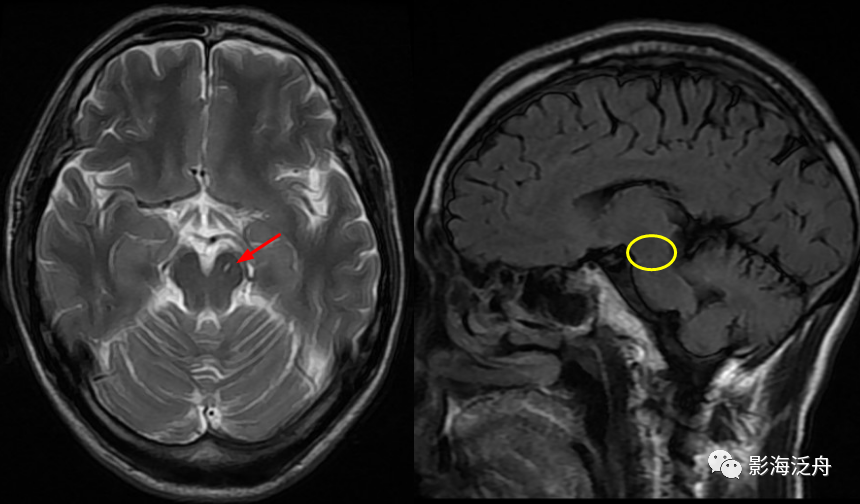

左侧基底节区腔梗灶,病灶既不像类圆形也不像规则的长条状,在Flair序列上灶周可以看到淡淡的高信号影(红箭)。基底节区的腔梗灶位置相较于扩大VR腔隙往往更加靠近上份层面、形态不规则,且随着病程时间延长Flair序列高信号会愈加明显。

左侧基底节区腔梗灶(红箭头),尽管后部的那个病灶看起来有点圆,但在Flair序列病灶周围可以看到非常明显的高信号(绿箭),代表局部胶质增生,证明其为慢性期腔梗灶而非扩大的VR腔隙,其余病变(黄箭)为对称性分布,呈斑点状或长条状,Flair序列灶周无高信号,诊断VR腔隙更为合理。